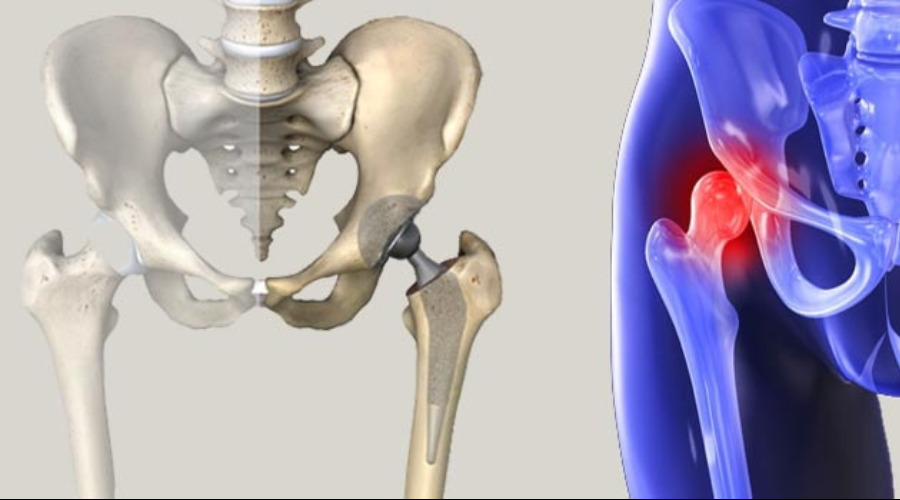

Замена таз сустава

Замена таз сустава 113 фотографий